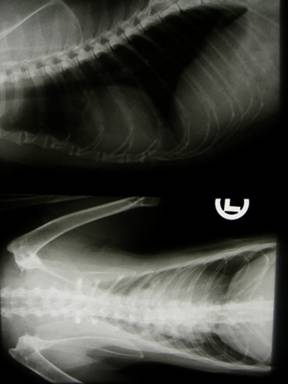

Röntgen: |

Flüssigkeitsansammlung im Thorax (rote Pfeile) und vergrößerte Herzsilhouette |